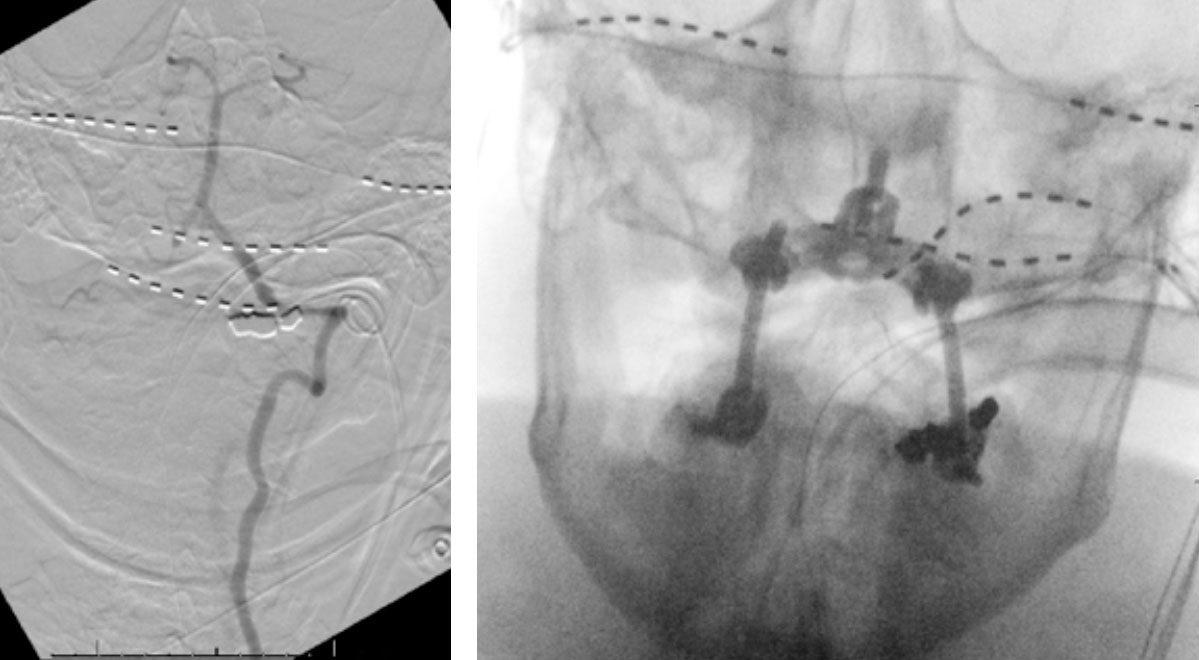

We performed conventional catheter angiography with provocative testing to reproduce his symptoms. The right Vertebral Artery is the codominant primary supply to the basilar circulation with reflux into the distal left Vertebral Artery that is occluded (Figure 3).

During neutral positioning, the vertebrobasilar circulation fills briskly from the Right Vertebral Artery. (Figure 4)

On rotation to the left, the patient experienced mild symptoms, however no significant Vertebral Artery or basilar reduction in flow was observed. On rotation to the right, the patient experiences slightly more moderate symptoms, however no significant Vertebral Artery or vascular reduction flow was observed. On hyper extension of approximately 10-15 degrees, passively performed by the patient until symptoms are reproduced, angiogram demonstrates complete occlusion of the right Vertebral Artery at approximately the C2-C1 level. (Figure 5)